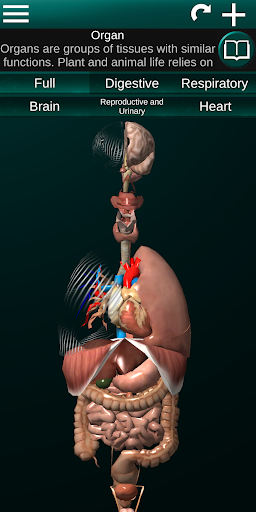

Показує 3D анатомічну модель основні органи людського тіла та опис кожного з них.

Що в додатку?

* Травна система, включаючи шлунок, тонку кишку, товсту кишку та анімацію цієї системи.

* Дихальна система, яка включає трахею, бронхи, легені та анімацію цієї системи.

* Легкий доступ і навігація (масштабування, 3D-обертання).